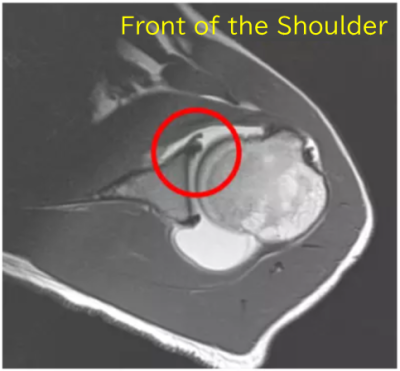

The diagnosis is made using an imaging test called contrast-enhanced MRI.

A saline solution mixed with contrast agent is injected into the shoulder joint, and MRI scanning is performed.

In the illustration below, the blue circle indicates where the contrast agent has collected — it leaks into the area of the injury.

Normally, the labrum is tightly attached to the glenoid.

If it is detached, fluid flows into the gap.

The contrast agent helps make these findings more visible on MRI.

The red circle shows where the contrast agent has entered the area of injury.

The damaged area is small, and this finding is visible in only a few slices out of the many taken.